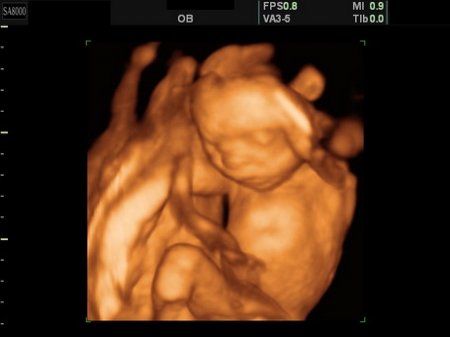

Видео и УЗИ

Разумеется, будущим мамам интересно не только знать, как происходит развитие их малыша, но и наблюдать за процессом. Современные технологии позволяют беременным наблюдать весь процесс на видео. Тем не менее, врачи не рекомендуют слишком часто делать УЗИ обследование.

Проблема решается с помощью уже готовых многочисленных видео роликов. Это обусловлено тем, что развитие зародыша происходит в большей или меньшей степени одинаково, а значит, и на видео практически у всех вырисовываются одни и те же картинки.

Подробности об УЗИ и беременности на видео.